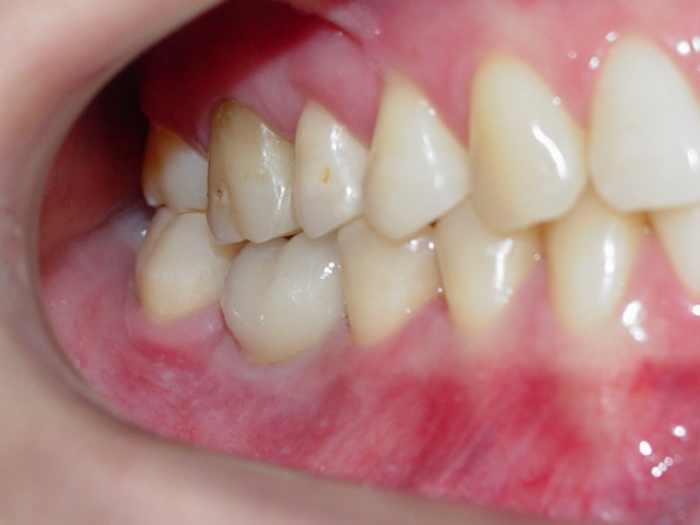

Imagens da prótese unitária sobre implante, do caso finalizado em janeiro de 2011